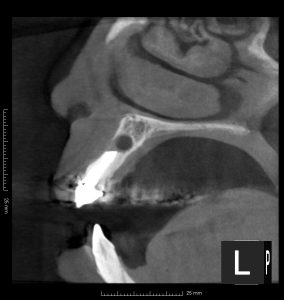

(術後1年のレントゲン、CT)

治療した3本とも、根尖部の骨は完全に再生しているのが確認できる。

術前にあった痛みの症状も、消失している。

患者さんも結果に満足しておられた。

マイクロスコープ下で行う歯根端切除術+逆根管治療は、90%という高い成功率を誇る。

症例によっては、今回のように歯根端切除術のみで対応できるケースもある。